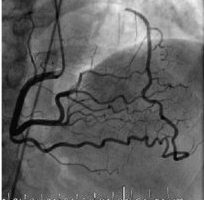

- Revascularisable or Non-revascularisable HF (STICH study responders)